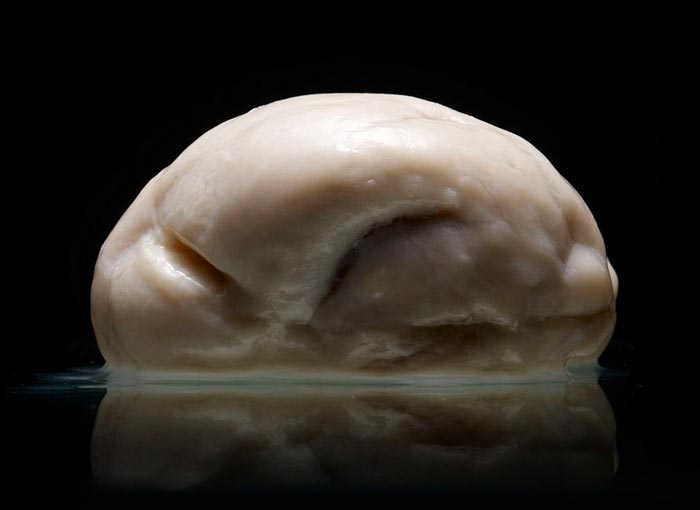

“Some of them are huge, some of them are really tiny. There was one that had no wrinkles at all,” he told Co.Exist's Stan Alcorn “I don’t even know how to explain it.” He became interested in documenting the collection and after agreeing on the details, Voorhes spent a weekend setting up a studio in the brain lab and created 230 photographs over a two day weekend.